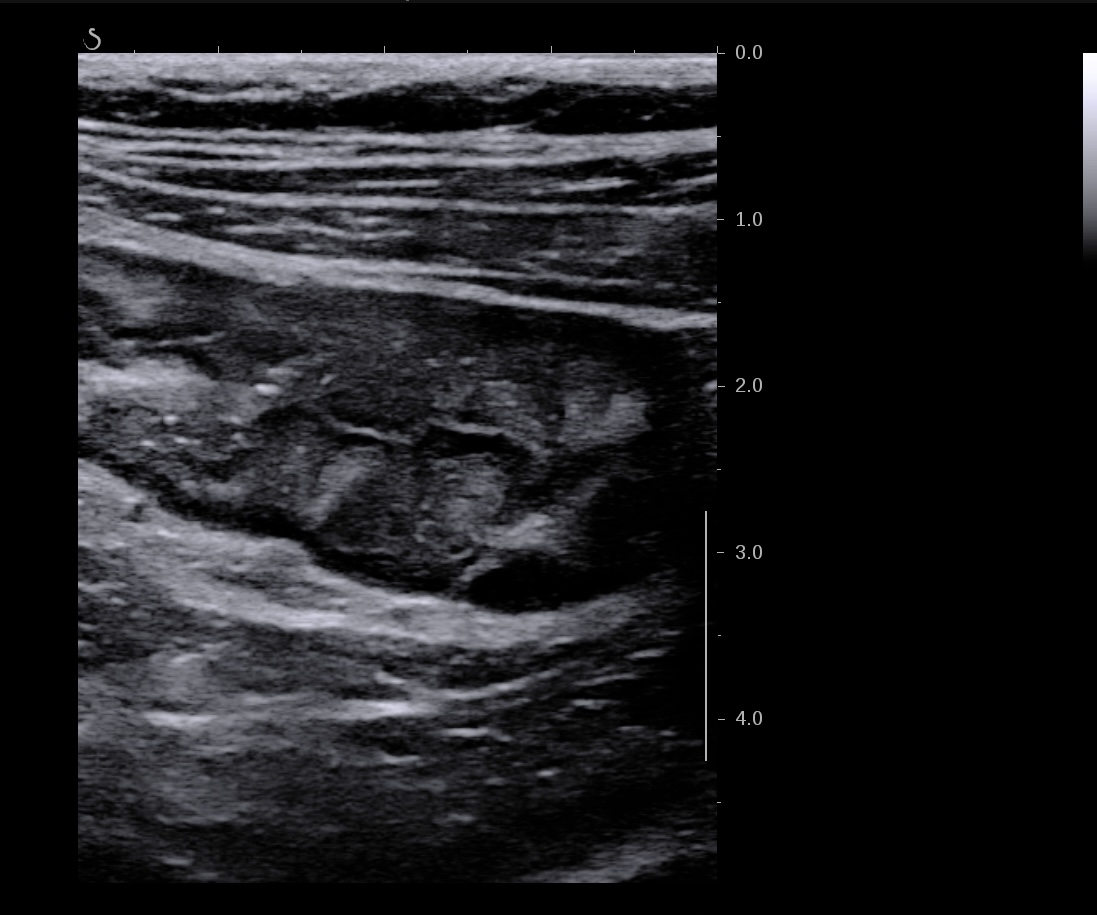

Là encore la paroi est très hypoéchogène, la structure en couches est par endroit totalement absente, ulcérations en surface, infiltration de la graisse, doppler intense, petites adénopathies périphériques.

Le rectum est bien vu avec la sonde basse fréquence la paroi atteint 10 mm à ce niveau.

Le score de Milan MUC est de (10 x1,4+2) = 16